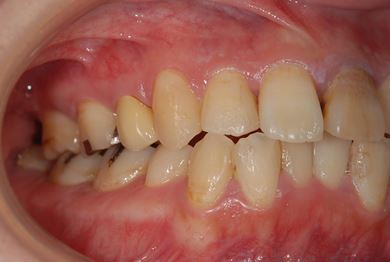

性別/年齢 女性 / 26歳

主訴 虫歯や汚れの治療を希望。

治療方針 セラミック治療にて、審美的回復を行う。

治療前

• 治療前